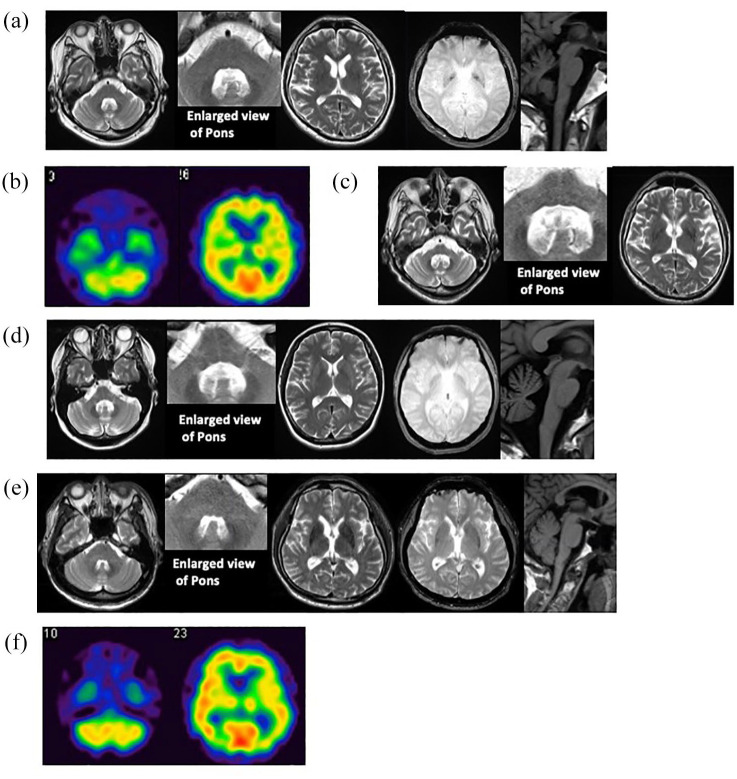

Parkinsonism-dominant multiple system atrophy (MSA-P) is typically a progressive disorder with poor responsiveness to levodopa and an unfavorable prognosis. However, in certain cases, the response to levodopa can be as robust as in Parkinson's disease (PD), with severe motor fluctuations developing during treatment. Unlike PD, no established therapy exists to maintain activities of daily living (ADLs) in such patients. We present three cases of young-onset MSA-P who demonstrated sustained levodopa responsiveness and were treated with levodopa-carbidopa intestinal gel (LCIG) following the emergence of disabling motor fluctuations. In all three patients, parkinsonism was the predominant symptom from onset until LCIG initiation, with only mild autonomic or cerebellar symptoms. Prior to LCIG introduction, their motor complications closely resembled those of advanced PD. LCIG therapy successfully reduced "off" time and dyskinesia in all cases. However, long-term follow-up revealed a gradual decline in ADLs due to disease progression. These cases suggest that LCIG may be a valuable treatment option for selected MSA-P patients with preserved levodopa responsiveness.

Abstract Image